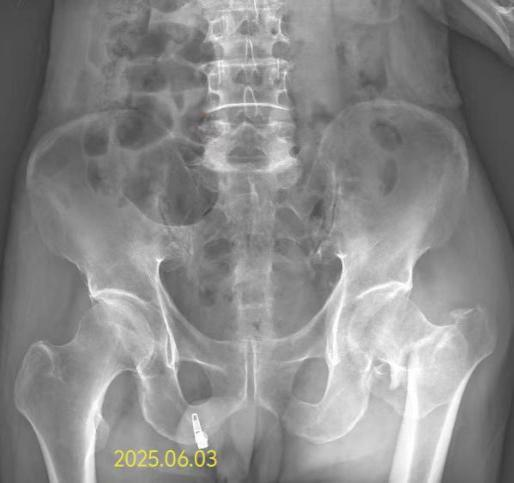

76岁的戴爷爷患脑梗后遗症、高血压病已有多年,日常生活完全依赖家人照料。今年6月3日,老人在家中不慎摔倒,左髋部剧烈疼痛,无法活动,家人紧急将其送往我院救治。

经检查确诊戴爷爷为左股骨粗隆间粉碎性骨折。由于患者高龄,有脑梗、高血压等复杂情况,若采取传统开放手术,不但创伤大、出血多,而且术后感染和血栓风险极高。若采取保守治疗,患者长期卧床又可能引发压疮、肺炎等致命并发症这让治疗陷入两难。面对挑战,我院骨科团队迅速组织神经内科、心内科、麻醉科进行多学科会诊,最终确定采用闭合复位髓内钉内固定术这一微创方案。